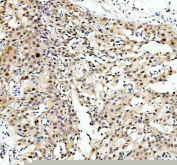

IHC staining of FFPE human bladder cancer tissue with NFAT5 antibody. HIER: boil tissue sections in pH8 EDTA for 20 min and allow to cool before testing.